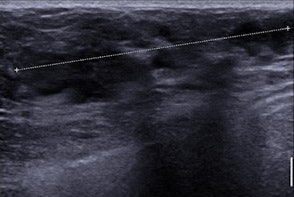

As previously noted, mammography was not the only modality used. On ultrasound, the precise description of margins improved the characterization of a mass, and in this study the two masses assigned BI-RADS ACR 3 at mammography (both TN) were classified BI-RADS ACR 4 at ultrasound because of their microlobulated or indistinct margins.

Regarding the correlation between ultrasound features and the different molecular classes, the most suspicious masses were more frequently seen in luminal tumors and oval masses with microlobulated margins, abrupt interface, and posterior enhancement in TN cancers, similar to the few correlations in the literature between ultrasound features and molecular phenotypes in all age groups.